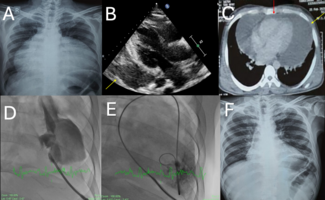

Both equation A and equation B in the present study are difficult to apply in daily clinical practice, since both equations require wedge pressure measurement during the maximum hyperemia. However, both equations are important when considering the theoretical background of the FFR assessment in a sequential lesion. Equation A suggests that the true FFR of individual stenosis is always smaller than the apparent FFR value. The severity of individual stenosis is always underestimated in multiple sequential stenoses. Equation B suggests that the true FFR of entire stenoses after releasing a given stenosis is always smaller than the apparent FFR value obtained by a simple addition of the baseline FFR plus ΔFFR across the target lesion. This is because the flow through the entire lesion increases after releasing a stenosis, which results in more pressure drop across the stenoses. Figure 7 represents a case with 3 sequential stenoses in the left anterior descending (LAD) coronary artery. The case clearly shows that after an intervention to the most severe stenosis, the ΔFFR across the other stenosis markedly increased. The postintervention FFR was smaller than the FFR calculated by a simple addition of the baseline FFR plus ΔFFR across the stenosis. The case clearly indicates that Equation A and Equation B provide a better understanding of the FFR assessment in sequential stenoses.